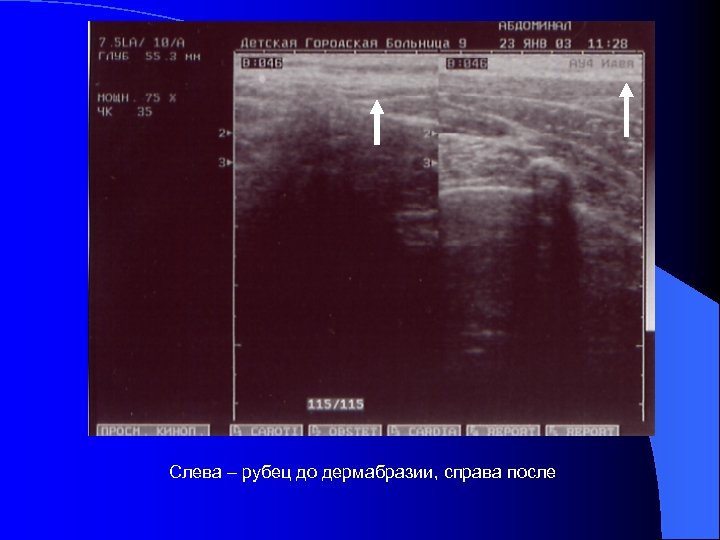

В отдаленном периоде ожоговой болезни при сформированных постожоговых рубцов, применяли СО 2 -лазер “Ланцет-2” для дермабразии этих образований. Производилось выравивание рельефа рубцов, устранение их гиперпигментации, сглаживание рубцовых границ пересаженных аутолоскутов, устранение мозаичности в участках аутодермопластики.

Слева – рубец до дермабразии, справа после